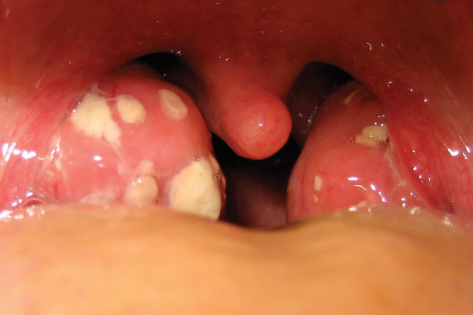

편도선염

편도선염의 증상은 고열, 오한, 인후통이 있고, 인두 근육에 염증이 발생하면 삼키는 동작이 힘듭니다. 또한 두통, 전신 쇠약감, 관절통 등 신체 전반에 걸친 증상이 나타나기도 하며 혀의 표면이나 구강 내에 끈적끈적한 점액이 생길 수 있습니다.이러한 증상은 4~6일 정도 지속되며 합병증이 없으면 서서히 사라집니다.목감기와는 다른 편도염은 증상이 심해질 경우 합병증은 물론 수술까지 해야 할 경우가 있습니다.